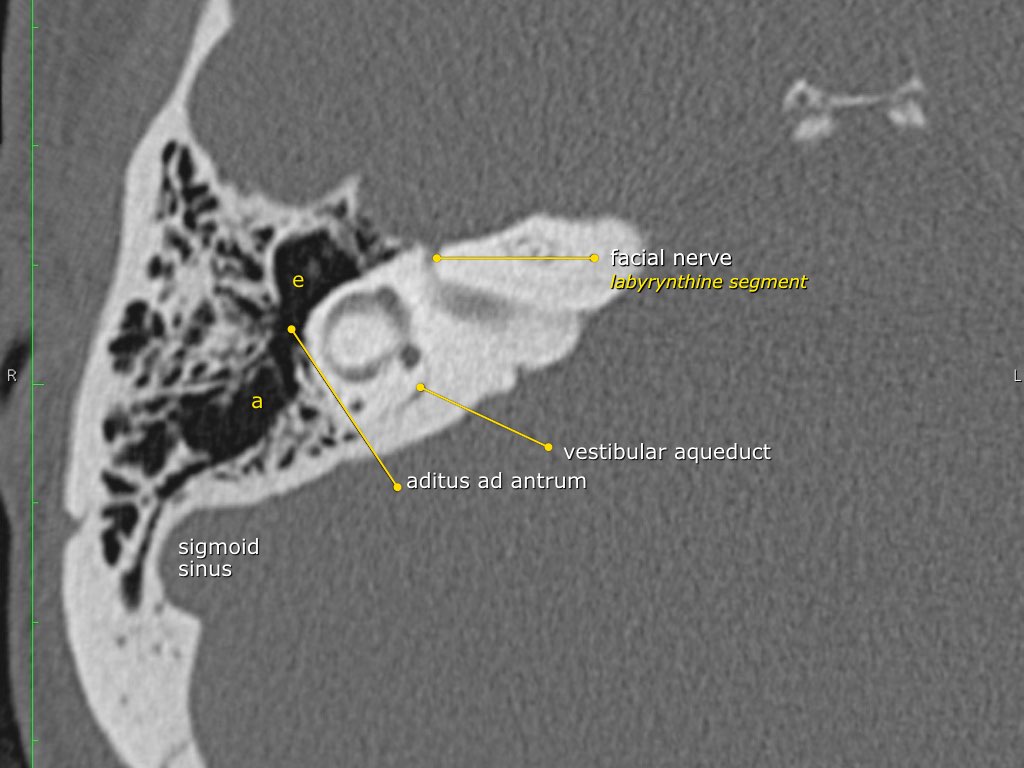

Thông qua ngách thượng nhĩ (aditus ad antrum), hòm nhĩ thông với hang chũm — một tế bào khí lớn nằm phía trên và phía sau hòm nhĩ — và thông với các tế bào khí chũm.

tạo nên lối vào xương chũm và được gọi là aditus ad antrum (lỗ thông hang).

Hang bào chũm là một tế bào khí lớn nằm phía trên và phía sau hòm nhĩ, thông với hòm nhĩ qua ngách hang (aditus ad antrum).

Đoạn mê nhĩ của dây thần kinh mặt xuất phát từ ống tai trong, chạy gần như vuông góc với trục dài của xương đá, gập góc nhọn về phía trước để đến hạch gối (geniculate ganglion).

Tại hạch gối, dây thần kinh mặt tạo thành một khúc quặt hình chữ U (genu thứ nhất của dây thần kinh mặt) để chạy ra phía sau theo đoạn nhĩ dọc theo thành trong của thượng nhĩ.